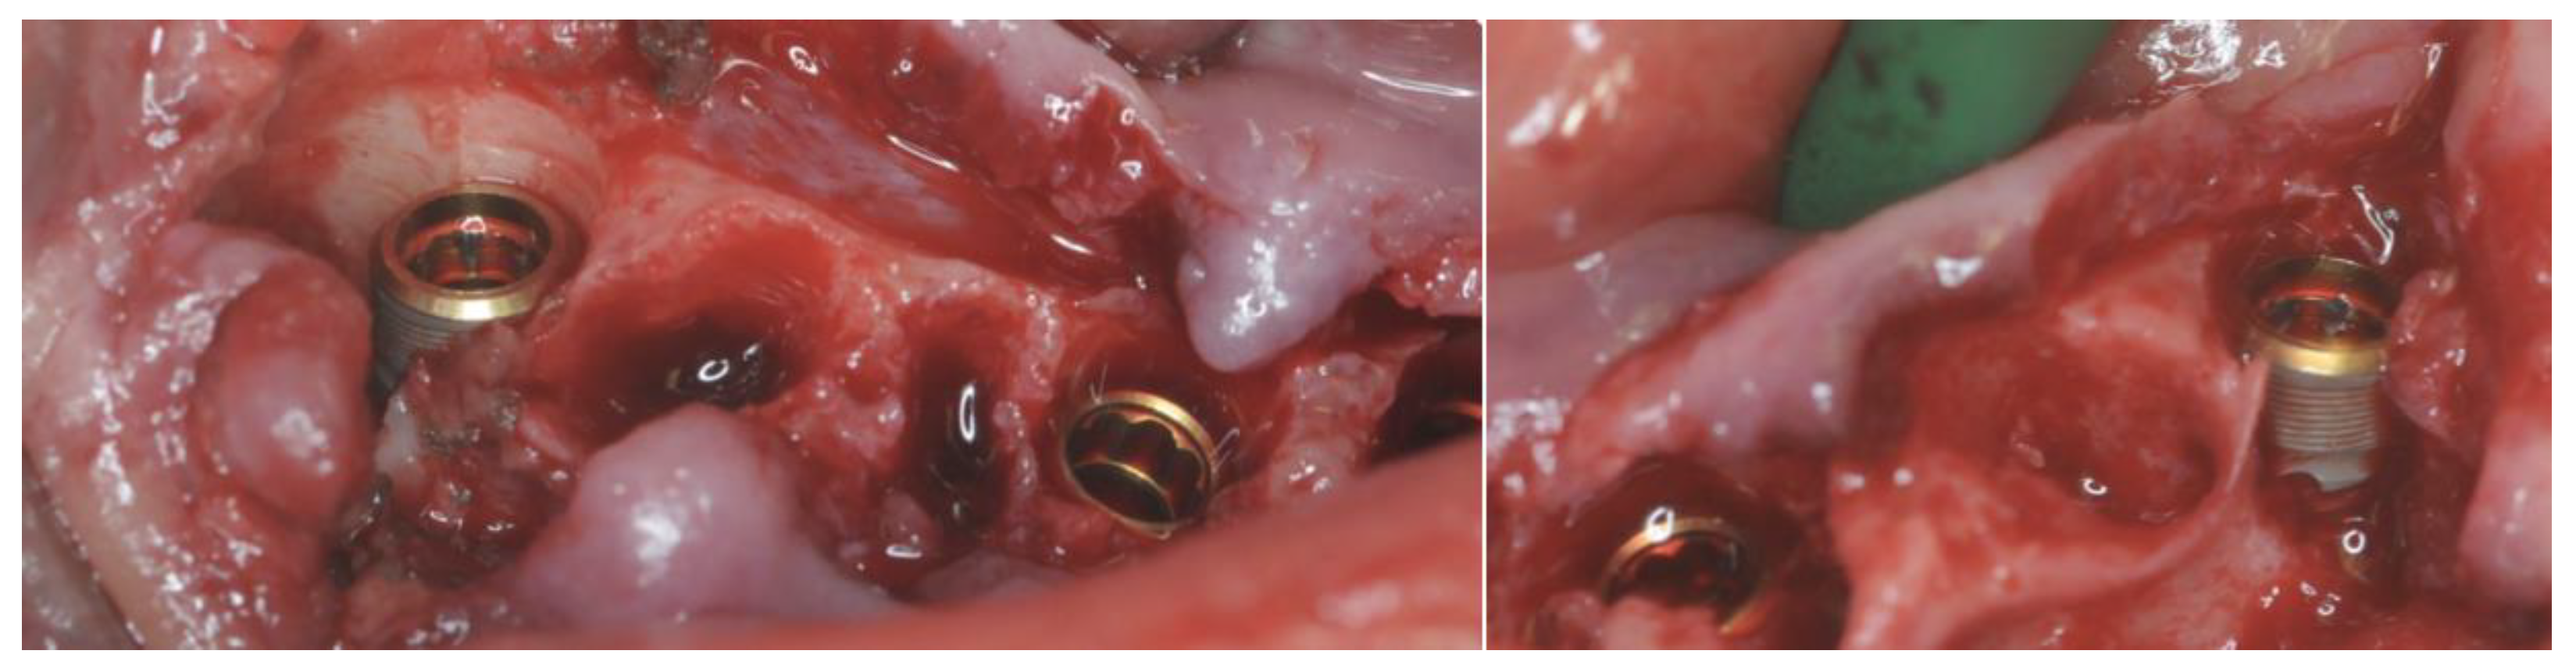

2.4. Surgery

2.5. Definitive Prosthesis